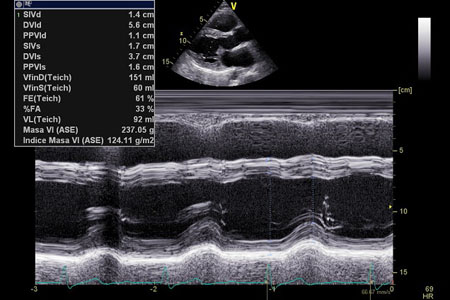

Diámetro diastólico del VI 56 mm (29 mm/m²), diámetro de fin de sístole 37 mm. No hay sobrecarga de volumen.

La fracción de eyección biplanar (automática) es normal (63%) así como los volúmenes ventriculares (diastólico 107, sistólico 39 ml).